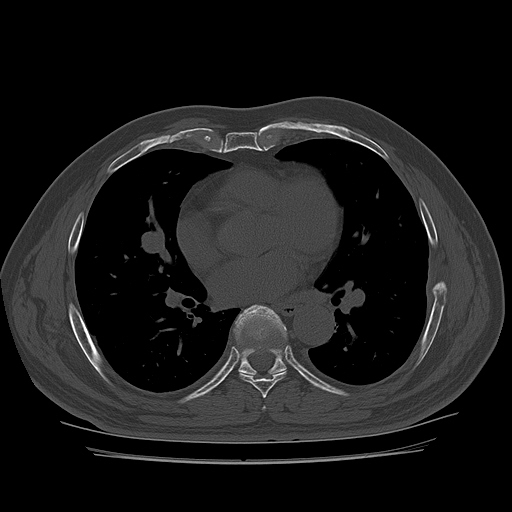

on moving of prove a little, there is bony protrusion(osteoblastic lesion) and hypoechoic(osteolytic)  lesion(image 2, 3, 4).

in transverse scan, visualization of osteoblastic mass with central osteolytic lesion(image 5, 6).

CT ; metastacic mass at rib and adjacent lung

As like this case, visualization of osteoblastic lesion and osteolytic lesion in simultaneously  suggests a malignant mass.

CT image